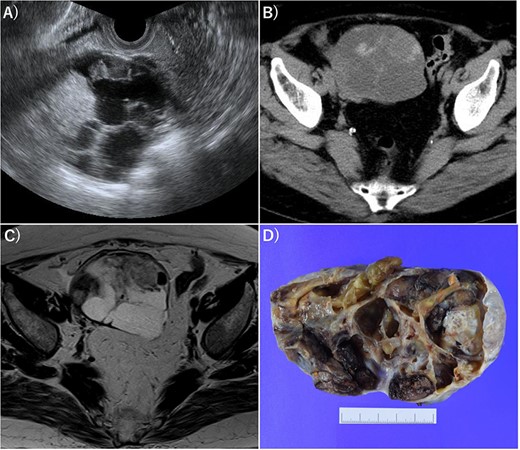

A 70-year-old female without any past medical history underwent total thyroidectomy and central neck dissection for PTC (pT3bN1aM0 pStage II; Fig. 1). Pre-operative blood examination showed a thyroglobulin (Tg) level of 351 ng/mL (normal value of Tg, ≤33.7 ng/mL). After surgery, her Tg level remained around 100 ng/mL (Fig. 2). However, 5 years after initial surgery, her Tg level increased to 366 ng/mL, with subsequent computed tomography (CT) revealing metastasis to the left III (Fig. 3) and right Vb and VI lymph nodes. CT also incidentally observed a right ovarian tumor, for which transvaginal ultrasonography and magnetic resonance imaging (MRI) were performed given suspicions of malignancy (Fig. 4). Blood examination showed a CA125 level of 33.4 U/mL (normal value of CA125, ≤35.0 U/ml). Given suspicions of malignancy by our hospital’s department of gynecology, total hysterectomy and bilateral adnexal resection had been conducted. A pathological diagnosis of OG with no malignancy was then established (Fig. 5). The patient’s post-operative Tg level decreased to 143 ng/mL (Fig. 2). For lymph node metastasis of PTC, right neck dissection and left III lymph node resection by sternal incision were performed. The left recurrent laryngeal nerve was resected due to the invasion of the left III lymph node. Though post-operative swallowing rehabilitation was needed, she was discharged 9 days after surgery with good clinical course. Post-operative blood examination showed a significant decrease in the Tg level (5.9 ng/mL).

Imaging of OG. (A) Transvaginal ultrasonography showed numerous separate structures and substantial nodules. (B) CT showed a 10.5-cm multifocal cystic tumor on the right side of the uterus. (C) Magnetic resonance imaging (T2-weighted image) revealed a tumor with numerous separate structures and substantial nodules, which led to speculations that the cystic area was serous. Right ovarian cancer was suspected. (D) Gross examination also showed numerous separate structures and substantial nodules.

Pathological diagnosis of OG was established (HE, ×100). Histologically, the right ovarian tumor showed large and small thyroid follicles with colloid, no papillary thyroid carcinoma nuclei and no malignant findings.